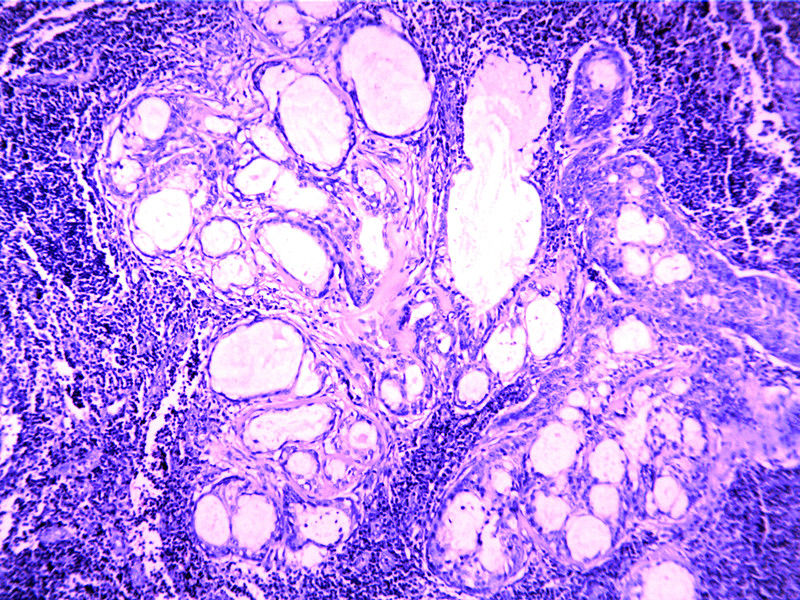

要想Hold住这个肿物的病理诊断,需要了解:

需要鉴别的肿瘤:

(1)皮脂腺淋巴腺瘤

(2)伴有淋巴组织间质的皮脂腺癌(皮脂腺淋巴腺癌)

(3)良性淋巴上皮病

(4)粘膜相关淋巴组织淋巴瘤(MALT淋巴瘤)

(5)转移性粘液表皮样癌